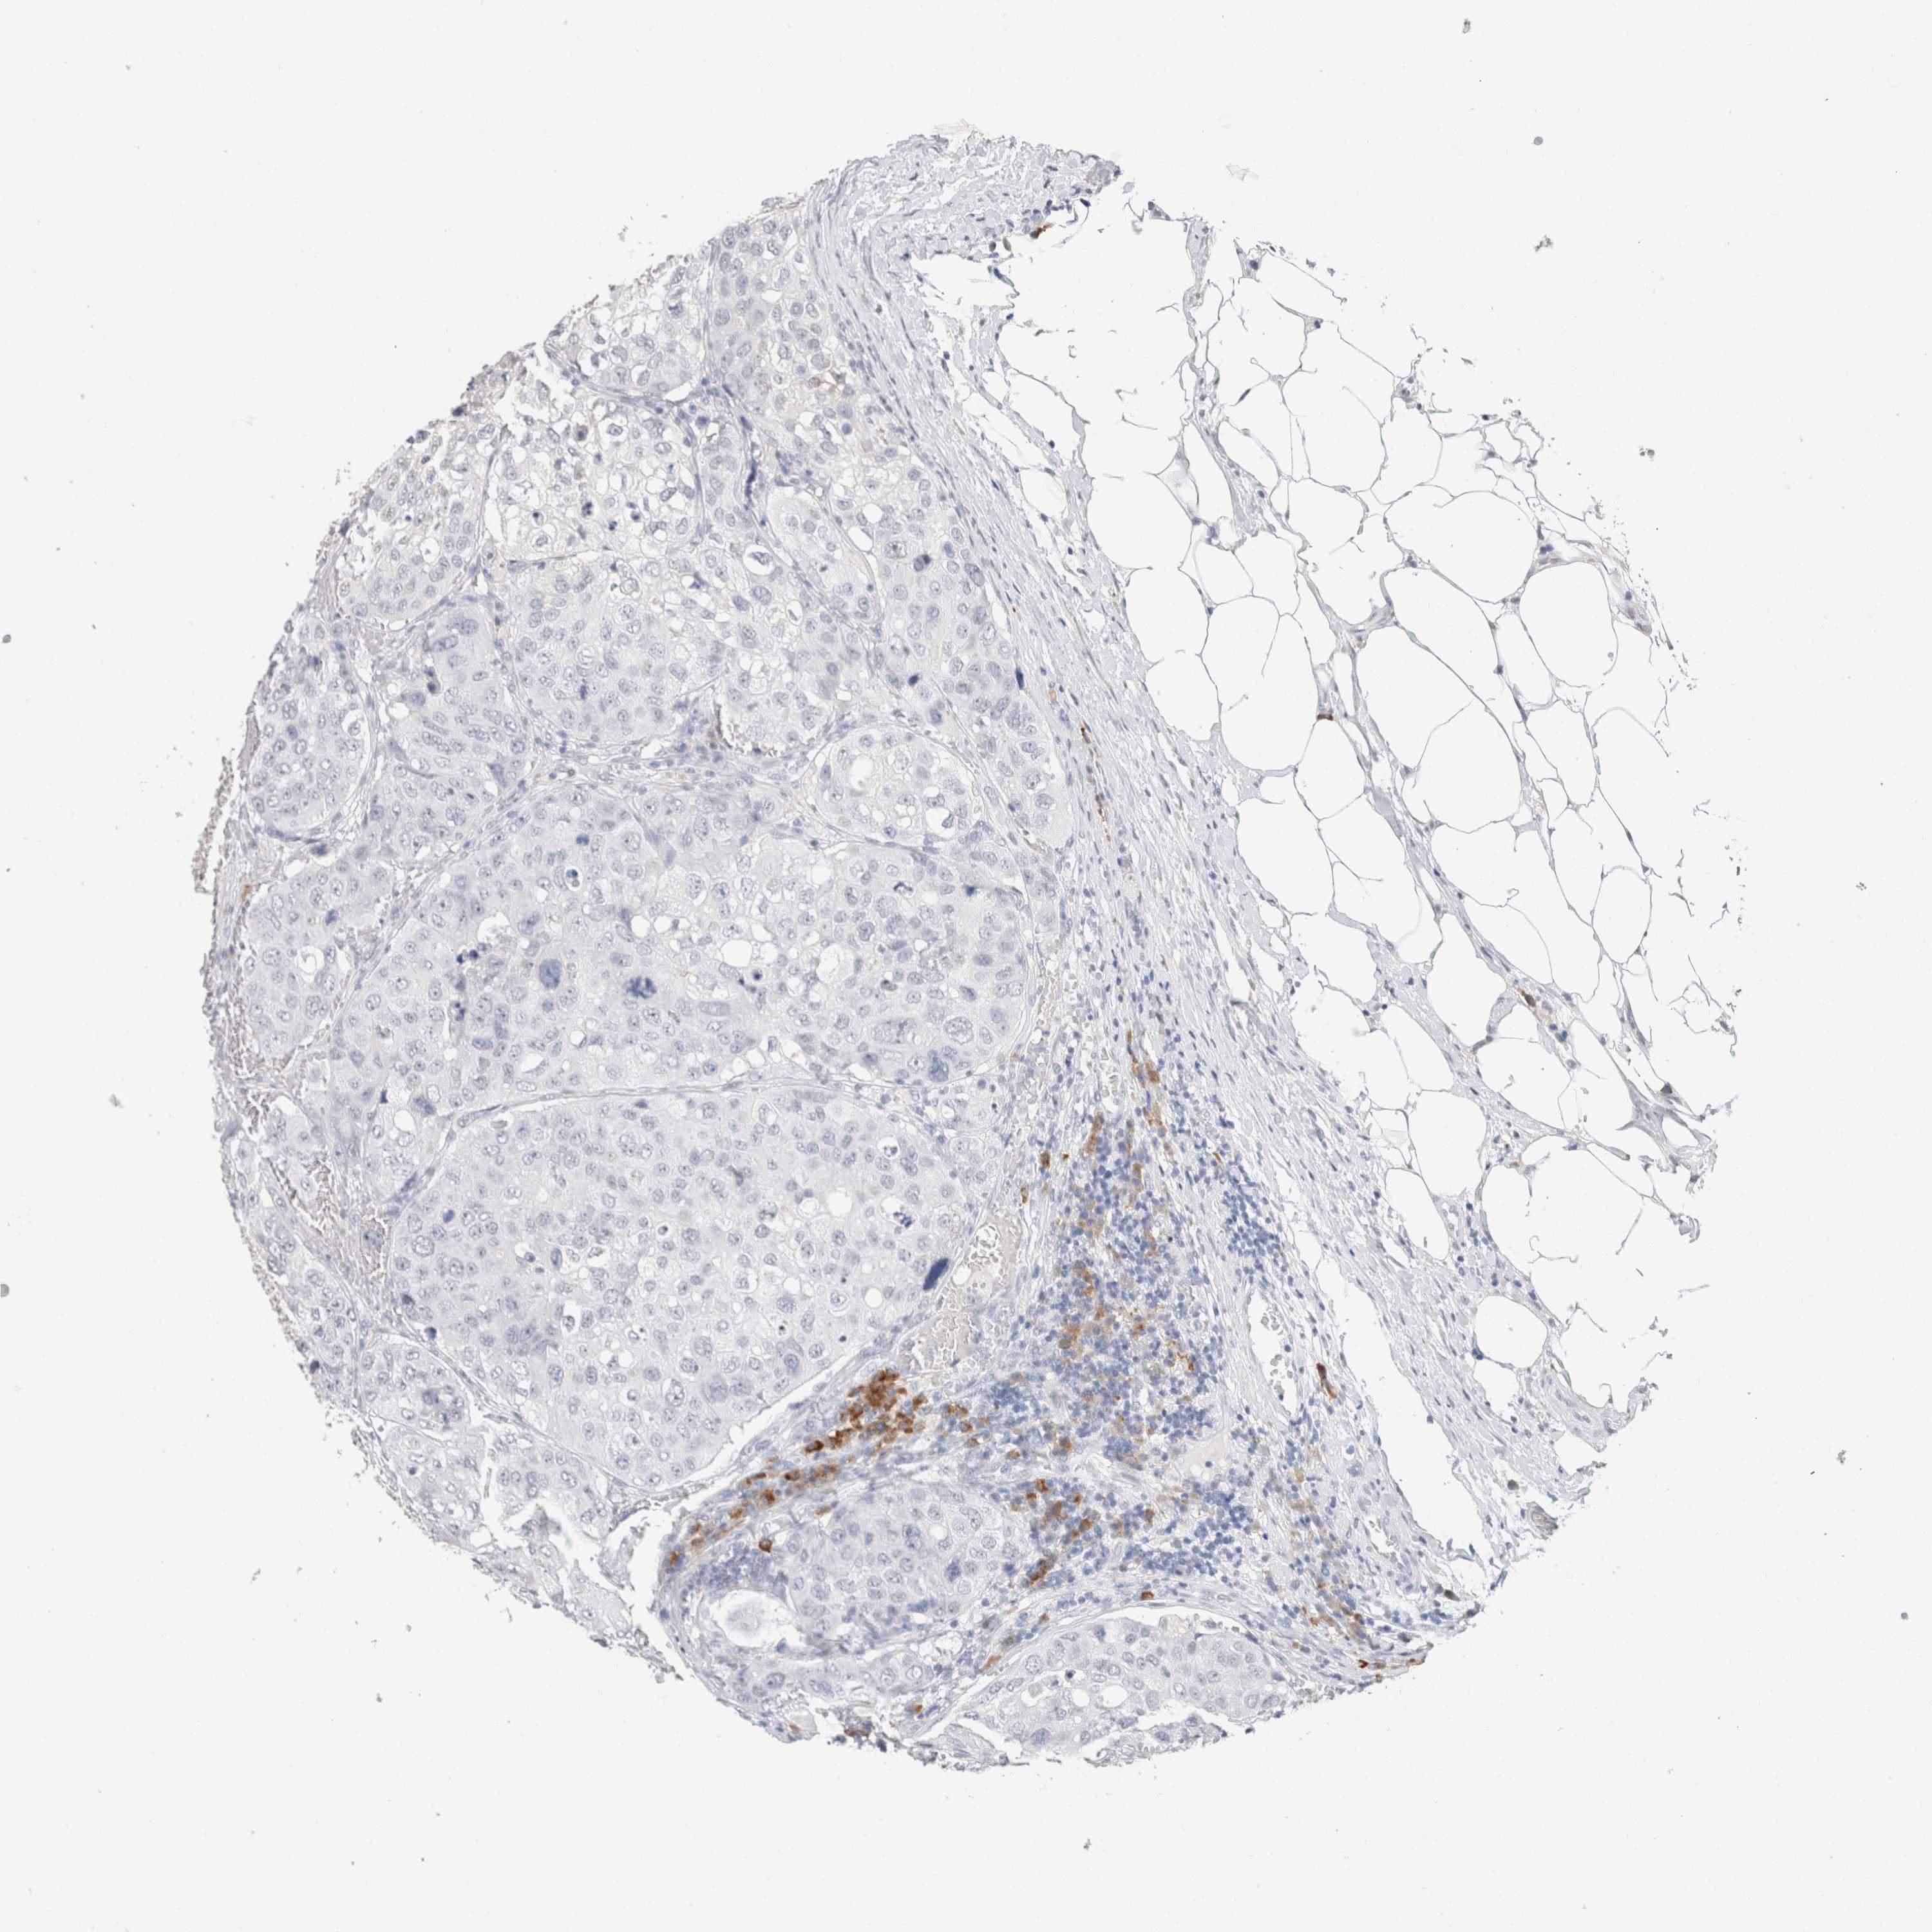

UROTHELIAL CANCER - Protein expressioni

A mouse-over function shows sample information and annotation data. Click on an image to view it in a full screen mode. Samples can be filtered based on level of antibody staining by selecting one or several of the following categories: high, medium, low and not detected. The assay and annotation is described here.

Antibody stainingi

Antibody staining in the annotated cell types in the current human tissue is reported as not detected, low, medium, or high, based on conventional immunohistochemistry profiling in selected tissues. This score is based on the combination of the staining intensity and fraction of stained cells.

Each image is clickable and will lead to virtual microscopy that enables deeper exploration of all samples and also displays staining intensity scores, fraction scores and subcellular localization as well as patient and tissue information for each sample.

Antibody HPA050092

Antibody CAB025368

Urothelial carcinoma, High grade

Urothelial carcinoma, Low grade